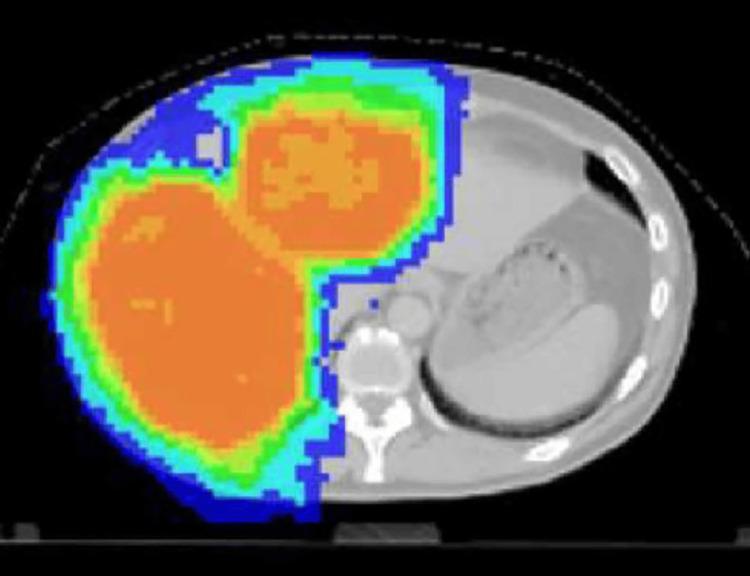

Among cervical cancers, small cell undifferentiated carcinoma is rare. Because of its rapid progression, the prognosis is extremely poor. During the course of cisplatin-based chemotherapy for stage Ⅳ small cell undifferentiated carcinoma of the cervix, the patient developed drug resistance, and standard treatment was no longer feasible. Therefore, immunoradiotherapy was administered to activate anticancer immunity. Surprisingly, the cancer drug sensitivity was restored, and cisplatin was again successful, and the cancer disappeared. In addition, the activation of cancer-specific immunity maintained the disappearance of the cancer. It should be noted that immunoradiotherapy not only increases anti-cancer immunity but may also contribute to overcoming cancer drug resistance.

在宫颈癌中,小细胞未分化癌较为罕见。由于其进展迅速,预后极差。在对一名Ⅳ期宫颈小细胞未分化癌患者进行以顺铂为基础的化疗过程中,患者出现了耐药性,标准治疗不再可行。因此,给予免疫放疗以激活抗癌免疫。令人惊讶的是,癌症药物敏感性得以恢复,顺铂再次取得成功,癌症消失。此外,癌症特异性免疫的激活维持了癌症的消失。应当注意的是,免疫放疗不仅能增强抗癌免疫,还可能有助于克服癌症耐药性。